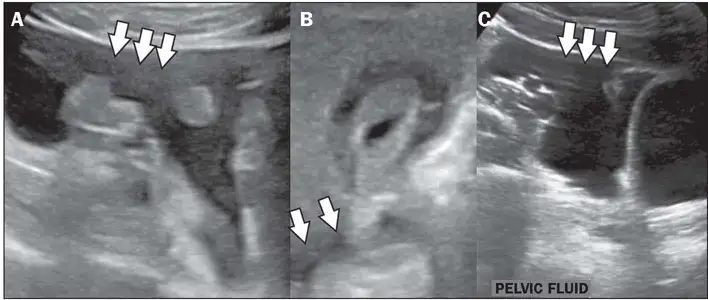

重症登革热的识别至关重要。世界卫生组织定义的预警信号包括:严重腹痛、持续呕吐、体液蓄积(腹水、胸腔积液)、黏膜出血、嗜睡或烦躁不安、肝脏肿大、红细胞压积升高伴血小板下降。任何出现这些预警信号的患者都应立即住院治疗。影像学检查在重症登革热的诊断和监测中发挥着重要作用。超声检查可以快速发现胆囊壁增厚、腹水、胸腔积液等典型的登革热表现,这些发现对于判断疾病严重程度和指导治疗具有重要价值。